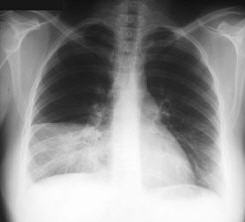

Этот вид пневмонии характеризуется поражением одной доли лёгкого, целого лёгкого или даже обоих лёгких. Чем больше объём поражения — тем тяжелее протекает процесс. Вызывается крупозная пневмония пневмококком. Кроме повреждения ткани легкого бактерия, выделяя токсичные для человека вещества, действует на весь организм – сильно повышается температура, появляется озноб.